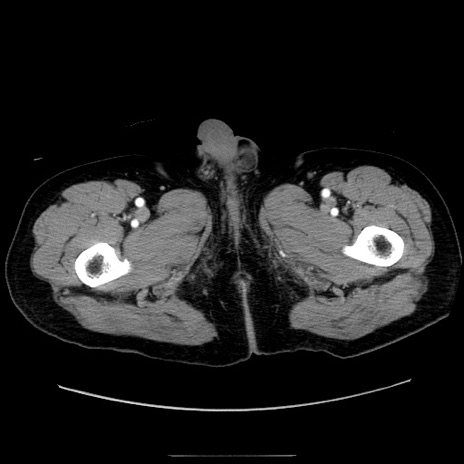

症例30(横断像)

【症例】80歳代男性

【主訴】臍周囲痛

【現病歴】約6時間前から臍下部痛が出現。次第に腹部膨隆・背部痛も生じてきたため来院。背部痛の場所は変化しない。

【身体所見】意識清明、BT 36.3℃、BP  131/87mmHg、P 87bpm、SpO2 100%(RA)、臍周囲自発痛・圧痛あり、反跳痛なし、自発痛部位に一致して板状硬あり、腹部膨隆、腸雑音減弱、CVA tenderness両側陰性。

【データ】WBC 19600、CRP 0.33